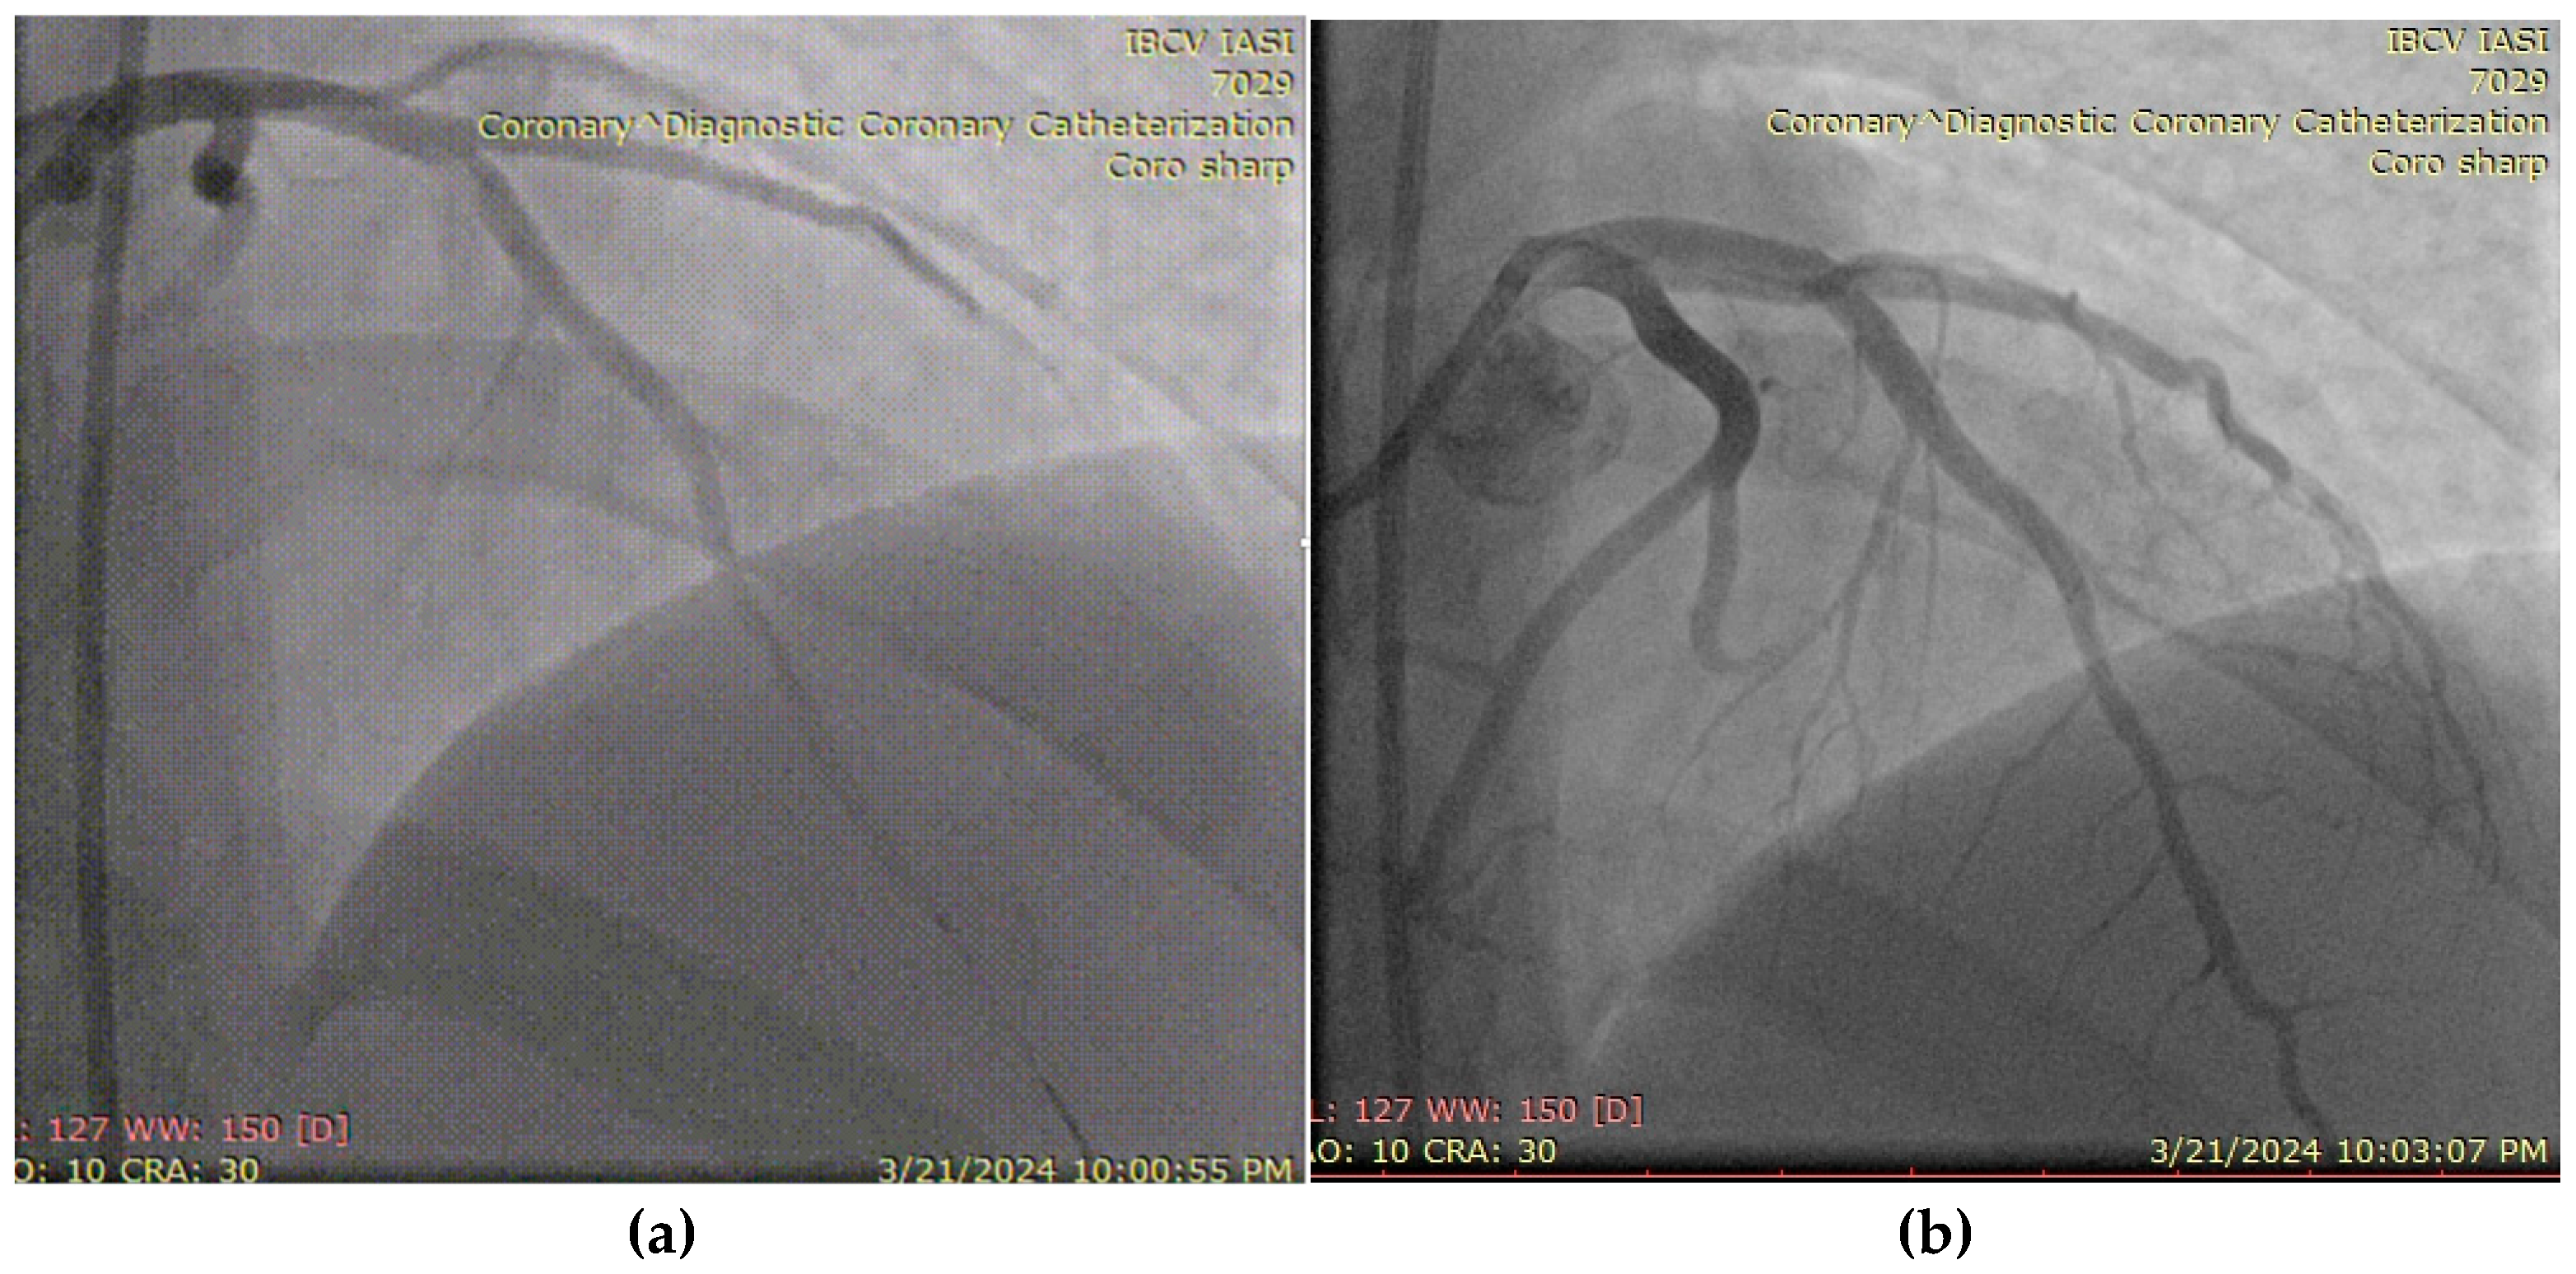

3.3. Case 3

3.4. Case 4